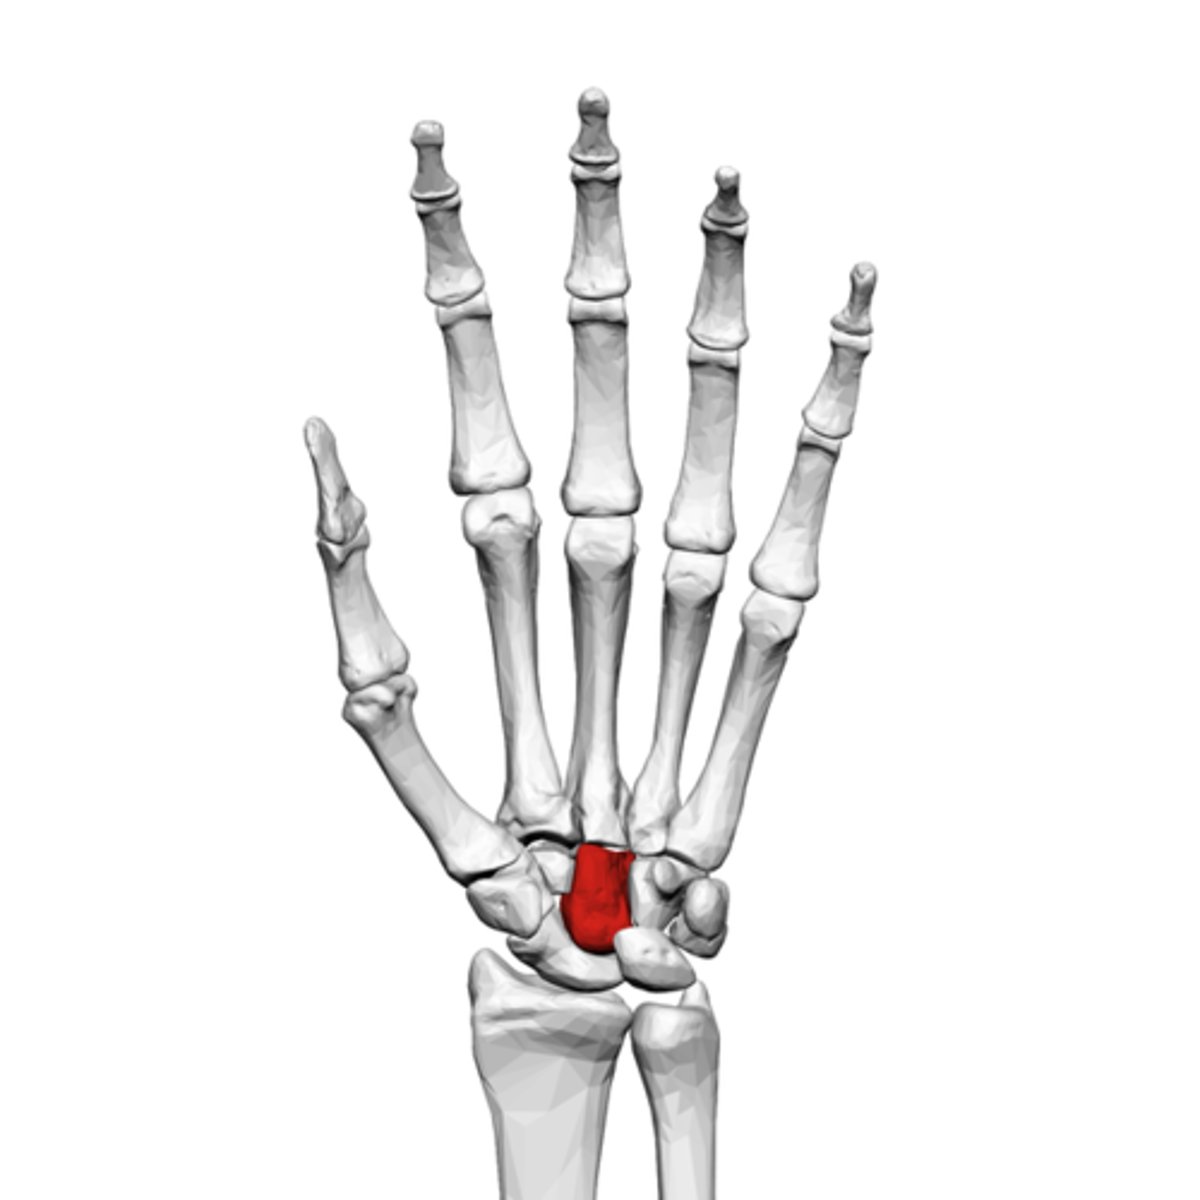

What is the term of the bones highlighted in red?

Trapezium

Trapezoid

Capitate